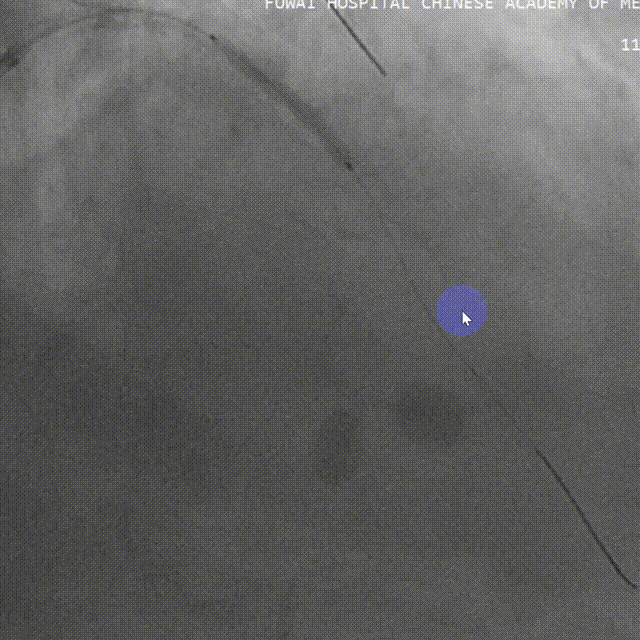

足位造影LM、LAD重度狭窄